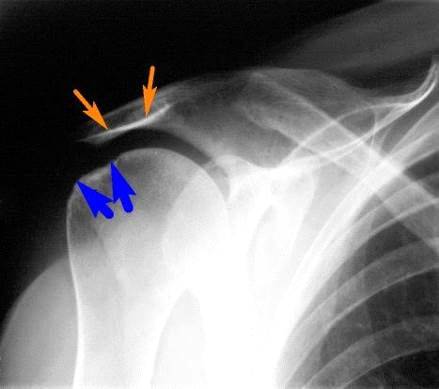

Первым исследованием, которое назначается больным с

подозрением на повреждение ротаторной манжеты, является рентегнологическое

исследование, однако оно не очень информативно.

Рис. 3 Рентгенограмма: соударение головки плечевой кости (синие стрелки)

и нижней поверхности акромиального отростка (рыжие стрелки) приводит к

повреждению проходящего между ними сухожилия надостной мышцы.

Для уточнения диагноза или объёма повреждения используется МРТ или

ультразвуковое исследование.